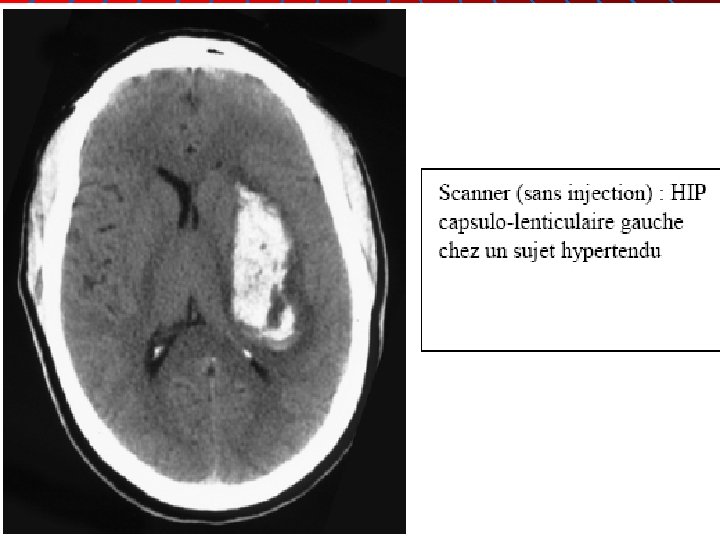

AVC hémorragiques (AVCh) Dr C PAURON SAU / SAMU / SMUR CHR Orléans (45)

1) Etiologies n n n HTA avec rupture de microanévrysmes (80% des AVCh). Malformations artério-veineuses (MAV) chez le sujet jeune. Tumeurs cérébrales sous-jacentes. Troubles de la coagulation (constitutionnels ou par traitement anticoagulant). Drogues (amphétamines, héroïne, cocaïne…)

2) Symptômes : Déficit brutal (ou rapidement progressif) n + céphalées n + vomissements n Chez un patient hypertendu. Troubles de conscience souvent